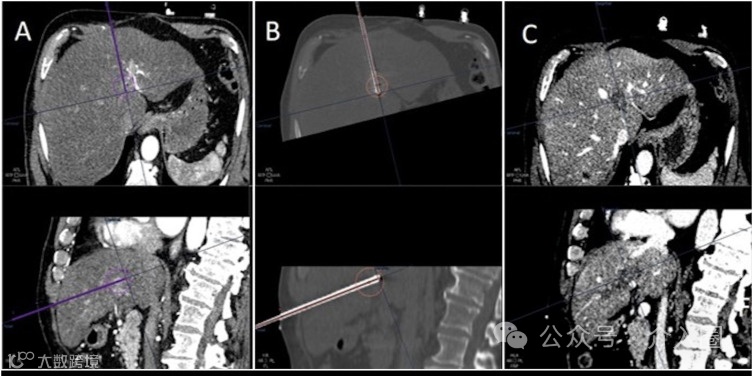

A. 计算机断层扫描(CT)图像显示了预定的穿刺轨迹和虚拟化的理论消融区域(上排:轴向视图;下排:矢状视图)。

B. 在热消融过程中进行的非对比度CT显示了插入的针头和基于实际针头位置的虚拟化的理论消融区域。

C. 治疗后的增强CT图像显示了消融区域的结果,目标覆盖完美,边缘良好。